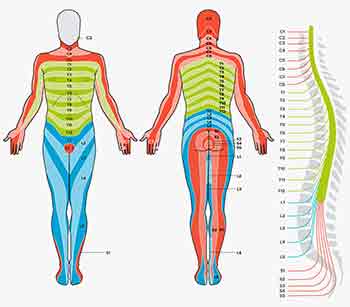

Back pain often means more than just giving you a pain in the back. It can create difficulties with walking, sitting, bending and lifting and can even lead to depression and breathing difficulties. It can also be the cause of pain in the buttocks, groin and legs, sciatica is a good example.

Back pain often means more than just giving you a pain in the back. It can create difficulties with walking, sitting, bending and lifting and can even lead to depression and breathing difficulties. It can also be the cause of pain in the buttocks, groin and legs, sciatica is a good example.Over 2.8 million adults in the UK of all ages suffer from long term back pain, enduring months and years of discomfort.

Acute pain arises suddenly and is most often due to muscle strain. Usually the spine is pulled out of line and mobility is severely restricted.

The muscles governing the movement in the painful area may have been in a hypertense state for years and have just had their 'last straw' placed on them. A nerve can be 'pinched' but more usually they become compressed due to swelling and/or muscle compression around the nerve roots. Usually there is an area of primary trauma with a secondary spread of pain, aching and stiffness which radiates outwards, upwards and downwards, thereby compounding the problem.

We can all experience nerve related symptoms. Ranging from pins and needles, numbness and partial paralysis of muscles and limbs. Most of these common symptoms can be relieved by the correct diagnosis and treatment. The more serious central nervous system conditions are more problematic but can still be greatly helped especially with their secondary symptoms such as weakness, loss of co-ordination and worse. The most common nerve related symptom is pins and needles in the hand. This may be due to a number factors and is often mis-diagnosed as carpal tunnel syndrome.

The correlation between what one is habitually doing with their body and the resultant pain patterns has become very clear over my years of studying and questioning patients. Many have found relief through what I deem to be simple, common sense observations. Patients will often present with fairly typical and predictable pain patterns. The noting of these patterns has inspired the creation of the ‘Pain Maps’ used in my online diagnostic projects.